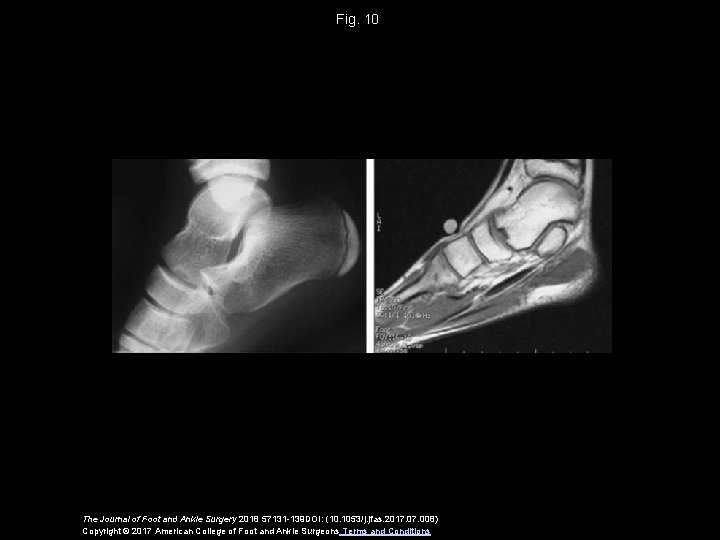

Fig. 10 The Journal of Foot and Ankle Surgery 2018 57131 -139 DOI: (10. 1053/j. jfas. 2017. 008) Copyright © 2017 American College of Foot and Ankle Surgeons Terms and Conditions